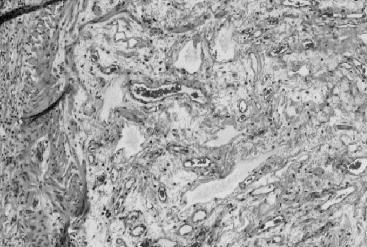

Microscopic se constată edem şi ţesut de granulaţie în submucoasă, cu elemente de maturaţie fibroasă (Fig. 3). Poate exista vasculită, iar epiteliul mucoasei este în general normal, cu rare elemente regenerative, posibil cu arii focale de ulceraţie.